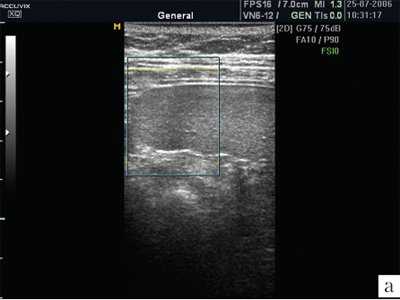

Капсула селезенки чрезвычайно тонкая, поэтому не визуализируется. Но благодаря капсуле изображение края селезенки предстает очень четким, хотя бывает сложно, особенно у полных пациентов, отграничить латеральный край селезенки от брюшной стенки. От капсулы селезенки в паренхиму отходят тончайшие соединительнотканные прослойки, которые намечают деление на дольки, хотя полностью дольчатого строения нет, поэтому орган очень хрупкий, особенно при спленомегалии, когда соотношение паренхимы и соединительной ткани резко изменяется в пользу первой составляющей. В норме эхографическое изображение селезенки гомогенное. Эхогенность селезенки у новорожденных, детей раннего и младшего возраста ниже, чем у взрослых, что объясняется слабым развитием трабекулярной ткани и полностью повторяет возрастную динамику эхоструктуры лимфатических узлов. Эхогенность ворот селезенки выше, чем ее паренхимы. В самой селезенке при использовании датчиков с частотой излучения 3-5 МГц регистрируется большое количество мелких линейных или точечных сигналов. Использование датчиков высокой частоты (13 МГц) позволило доказать, что эти сигналы являются отражением ультразвука от лимфоидных фолликулов (белой пульпы). Коэффициент корреляции с гистологическими находками оказывается очень высоким (r=0,71; p=0,03) [4]. Построение изображения в различных режимах открывает новые перспективы в возможностях оценки структуры селезенки. Ультразвуковое изображение селезенки в режиме МРТ позволяет лучше визуализировать паренхиму, убрать посторонние сигналы (рис. 1).

![УЗИ селезенки в обычном режиме]()

а) Изображение селезенки при ультразвуковом сканировании в обычном режиме. В паренхиме определяется множество дополнительных эхосигналов.